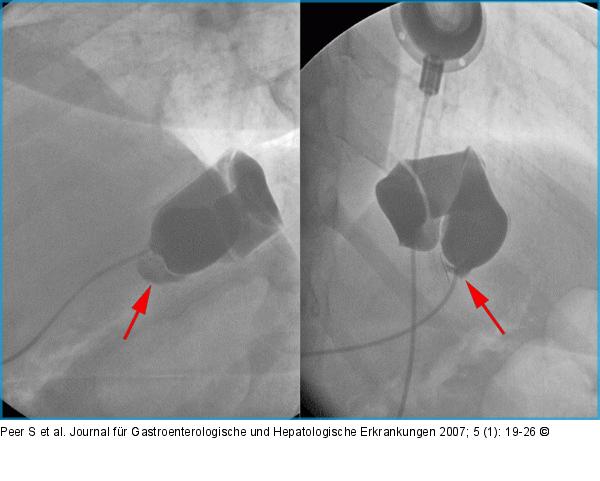

Abbildung 7: AGB Bandleck nach AGB: Nach Anspritzen des Bandsystems zeigt sich ein kleines Leck an der Anschlußstelle zwischen Katheter und Silikonband (Pfeile). |

Bandleck nach AGB: Nach Anspritzen des Bandsystems zeigt sich ein kleines Leck an der Anschlußstelle zwischen Katheter und Silikonband (Pfeile). |